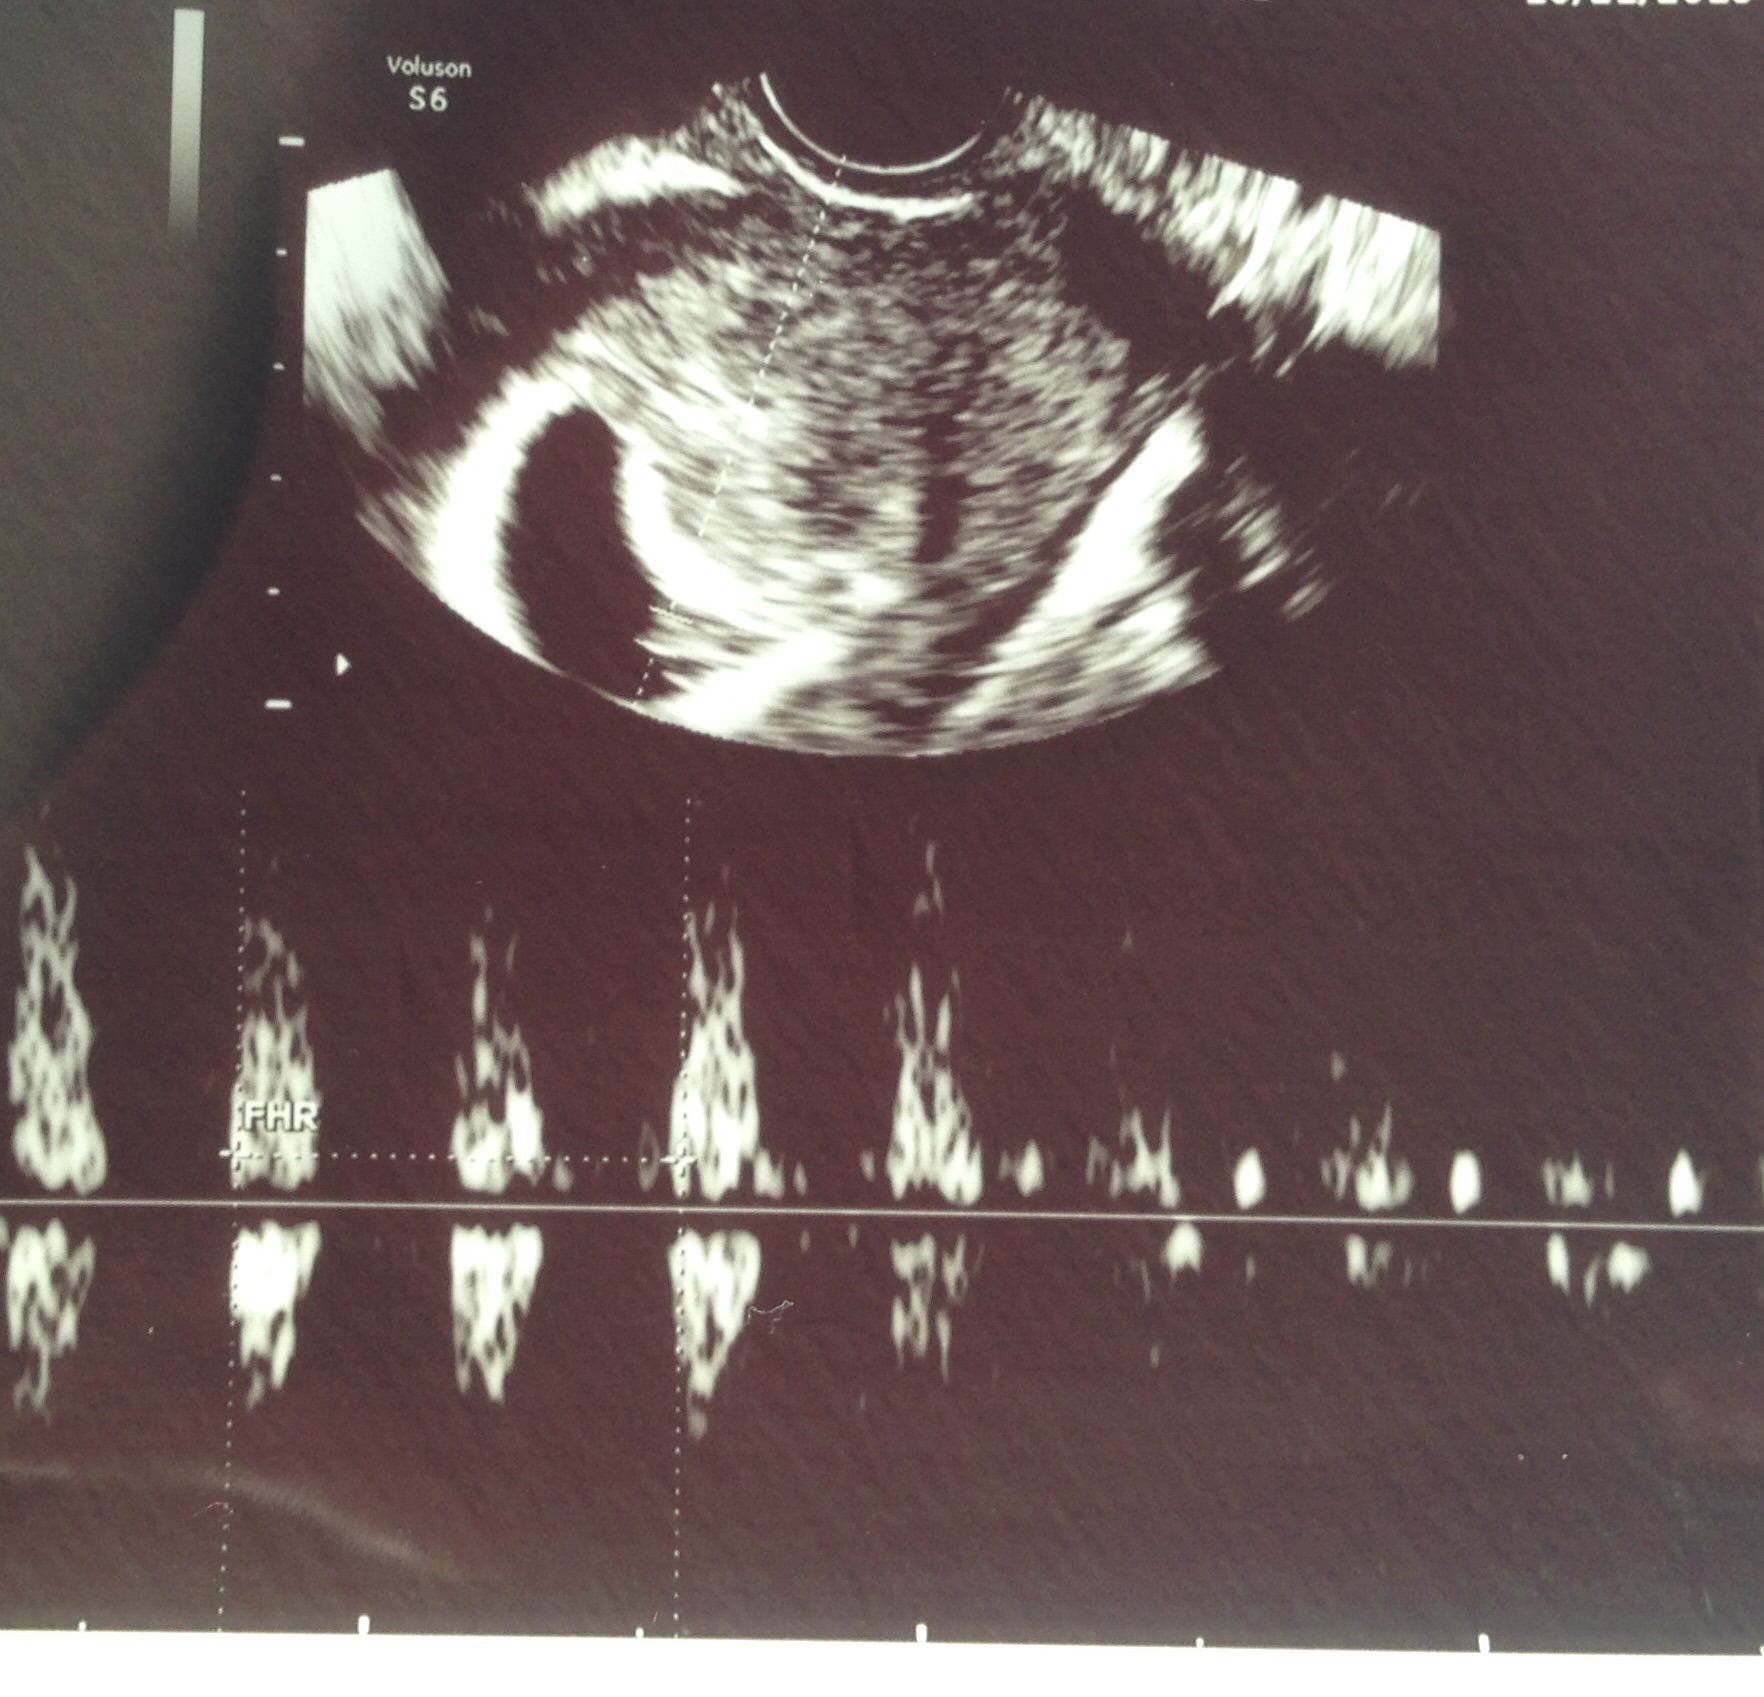

Had my dating u/s last night at 9w2d. Here's my little baby! We got to see the heart flicker! Heartbeat was 176 and they said s/he looks healthy. What an exciting experience that was!!!